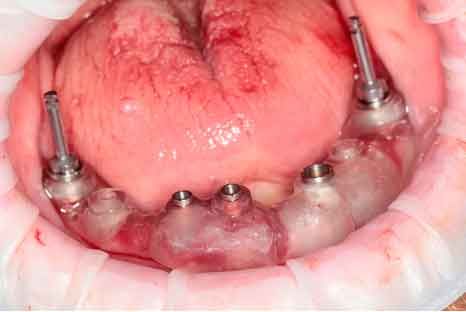

Patient de 66 ans. Souhaite retrouver un confort fonctionnel et améliorer l'esthétique.

Plaintes

- Manque de stabilité de ses prothèses amovibles

- Difficultés à manger

- Affaissement de la lèvre supérieure

Plan de traitement

Les structures parodontales des dents restantes ne sont plus suffisantes. Une édentation est envisagée. Le plan de traitement est orienté vers une prothèse complète maxillaire amovible et une prothèse complète mandibulaire supportée par des implants. Le défi est de passer de la situation initiale aux provisoires en utilisant les données du patient.

Photo - Situation intra-orale